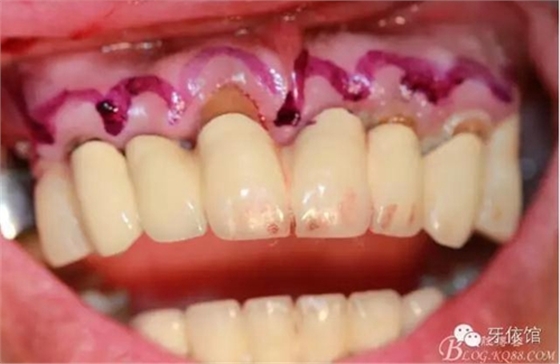

術(shù)中口內(nèi)照

降低骨高度,左右1,2骨寬度嚴(yán)重不足,決定將前牙2——2區(qū)間植體植在切牙孔內(nèi)

這個(gè)角度看1,2牙位骨寬度是不是很薄??jī)H2mm